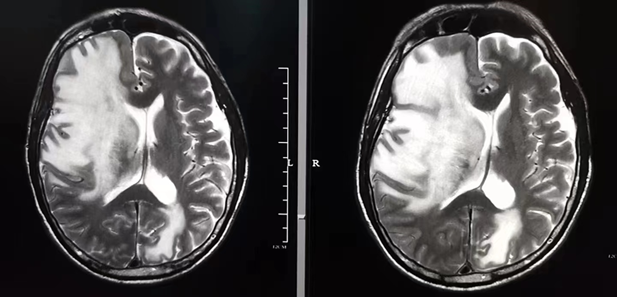

Brain glioma [ Therapy: P53 ]

From: HeRun

Date: 1 year+

Coma before admission

1 after treatment

2 after treatment